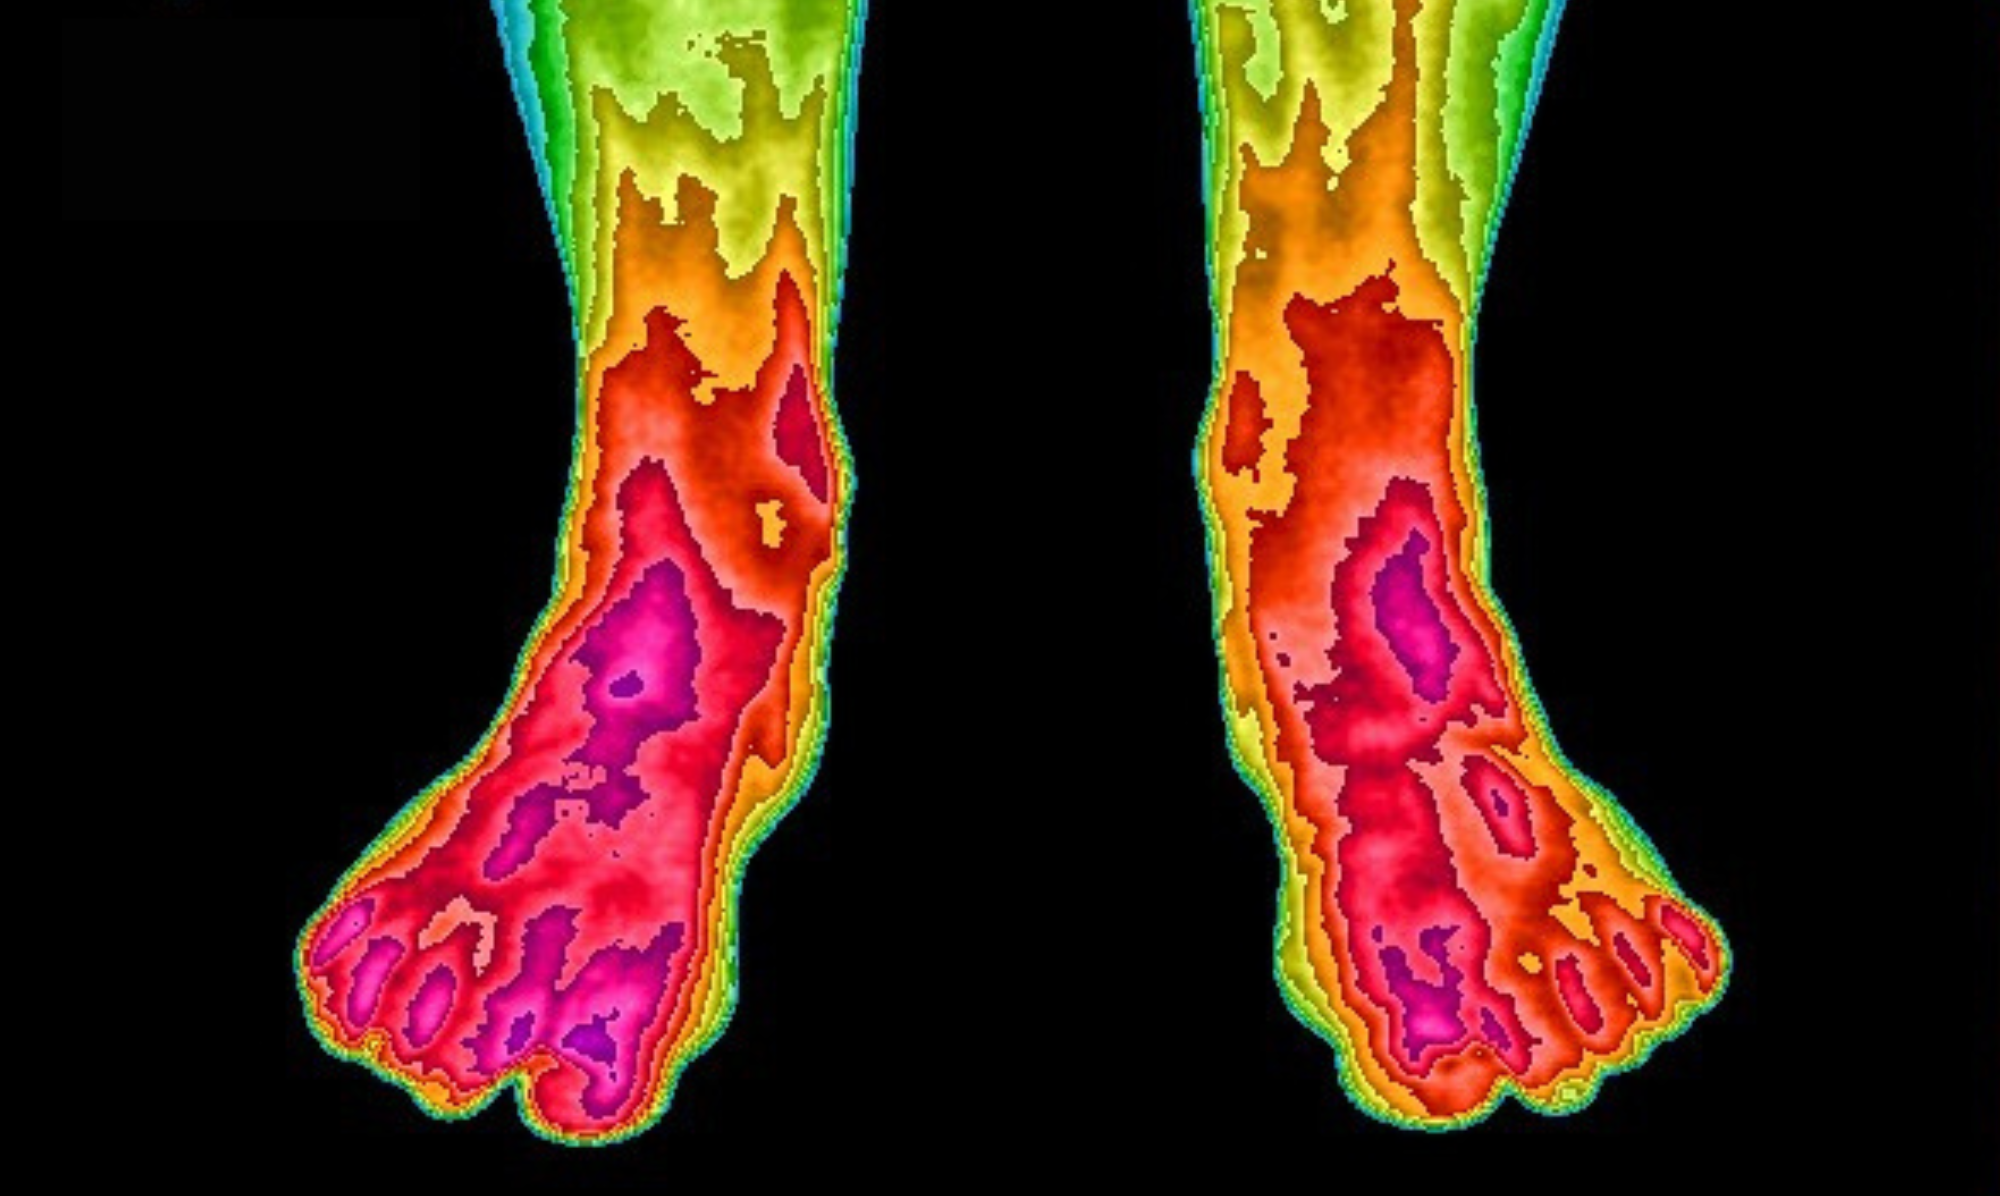

More than 26 scientific studies have examined grounding's positive effects on the human body. The infrared images shown here demonstrate blood flow changes after using our Earthing Mattress Cover for two weeks. Initially, toe circulation was nearly non-existent. Following the grounding period, healthy circulation returned to normal levels. This represents just one example from the extensive research conducted.

After

Before